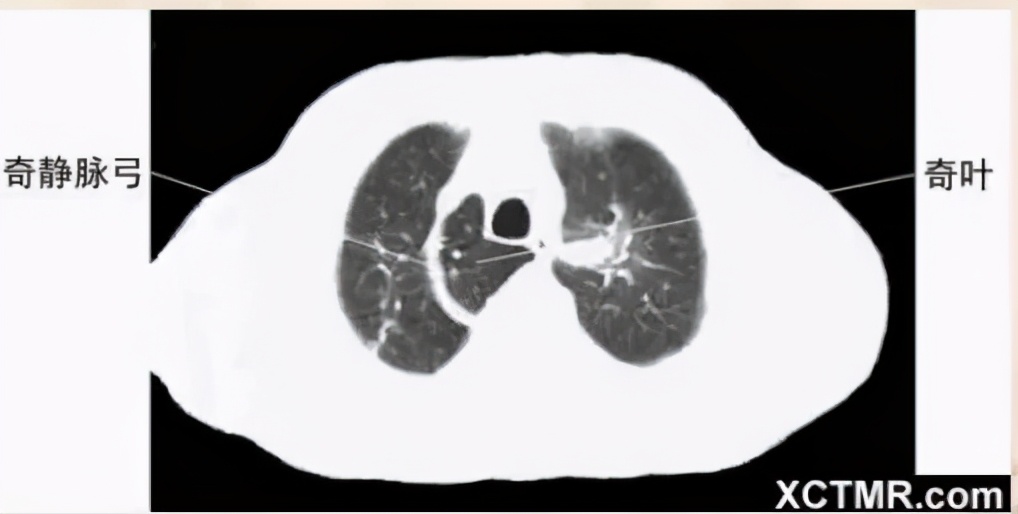

奇叶-奇静脉弓-胸膜分布